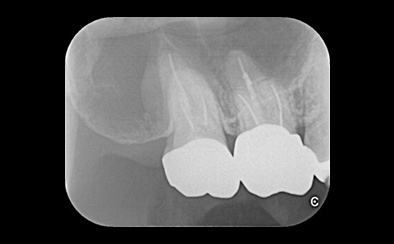

治療前

治療後

黄色い矢印の歯が治療前の対象歯です。レントゲンで観察すると、歯の根のお薬が充分には入っていないようです。

麻酔をして歯の中をマイクロスコープで観察すると、元々あった3つの根だけでなく「もう一つの4番目の根」があったのです。根管治療自体は容易に行えましたが、歯の中を明るく拡大できるマイクロスコープを持っていない歯医者さんでは見つけるのが困難だと思われます。この4つ目の歯の根を治療することにより痛みは消失し「抜歯してインプラント」になるという悪循環に陥らず済みました。根管治療はマイクロスコープを使って精密に、また丁寧に行えば歯を長く保たせることができる治療です。やはり神経自体を残すという選択が、歯の保存にとって一番良いということは間違いありません。

| 費用 | デンタルドック:55,000円 根管治療(奥歯):176,000円 MTAセメント:33,000円 歯の土台:33,000円 合計:297,000円 |

| リスク・副作用 | 治療中に一時的な咬合痛や冷温水痛、若干の歯肉の腫れ、発赤などを生じることがあります。また仮歯の時期には仮歯の脱離や破損の可能性、舌感などに違和感を覚えることがありますが、本歯に移行するまでに通常消失します。 ※すべて症例による違いや個人差があります。 |

※表示金額は全て税込みです。